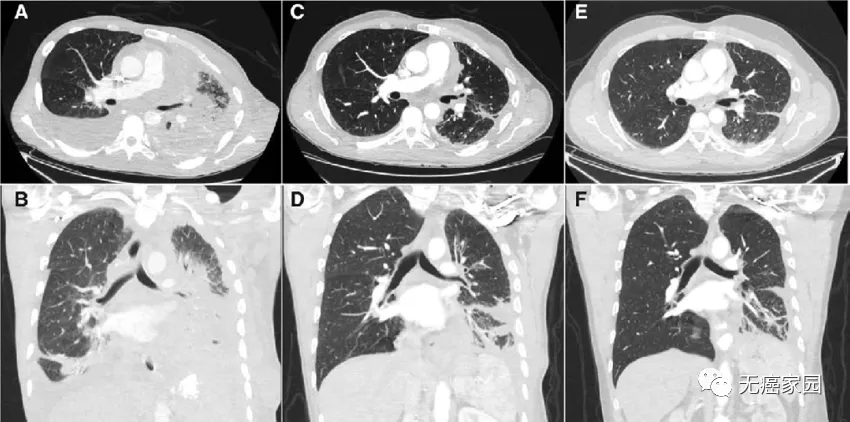

服药3周后,他的病情发生逆转!此前一直伴随的疼痛和呼吸困难症状消失了,全身的肿瘤缩小了46%。又坚持吃了5个月的药,全身肿瘤缩小了77%,之前转移到大脑处的癌细胞也没了!

患者对entrectinib的部分反应。entrectinib在第0-7天(基线扫描)、第26天(C、D)和第155天(E、F)时胸部的水平(A)和冠状位(B)图像。

这是NTRK融合阳性非小细胞肺癌的首次反应,也是使用NTRK抑制剂治疗后中枢神经系统转移性疾病的首次反应。